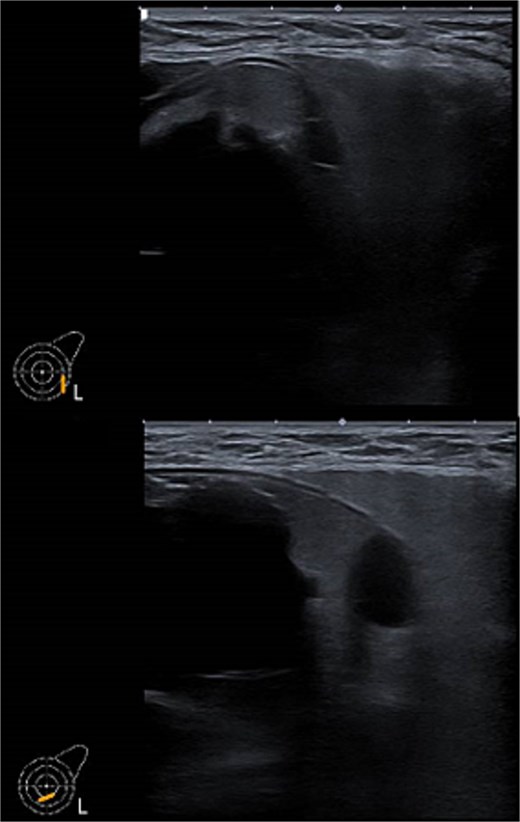

Ultrasound of left breast and axilla: Revealed rupture of the left implant with intracapsular and extracapsular leakage, along with echogenic peri-implant fluid. Enlarged axillary lymph nodes were visualized (Figs 1 and 2).

Ultrasound of the left breast showed rupture of the left breast implant with intracapsular and extracapsular leakage, surrounded by echogenic peri-implant fluid.